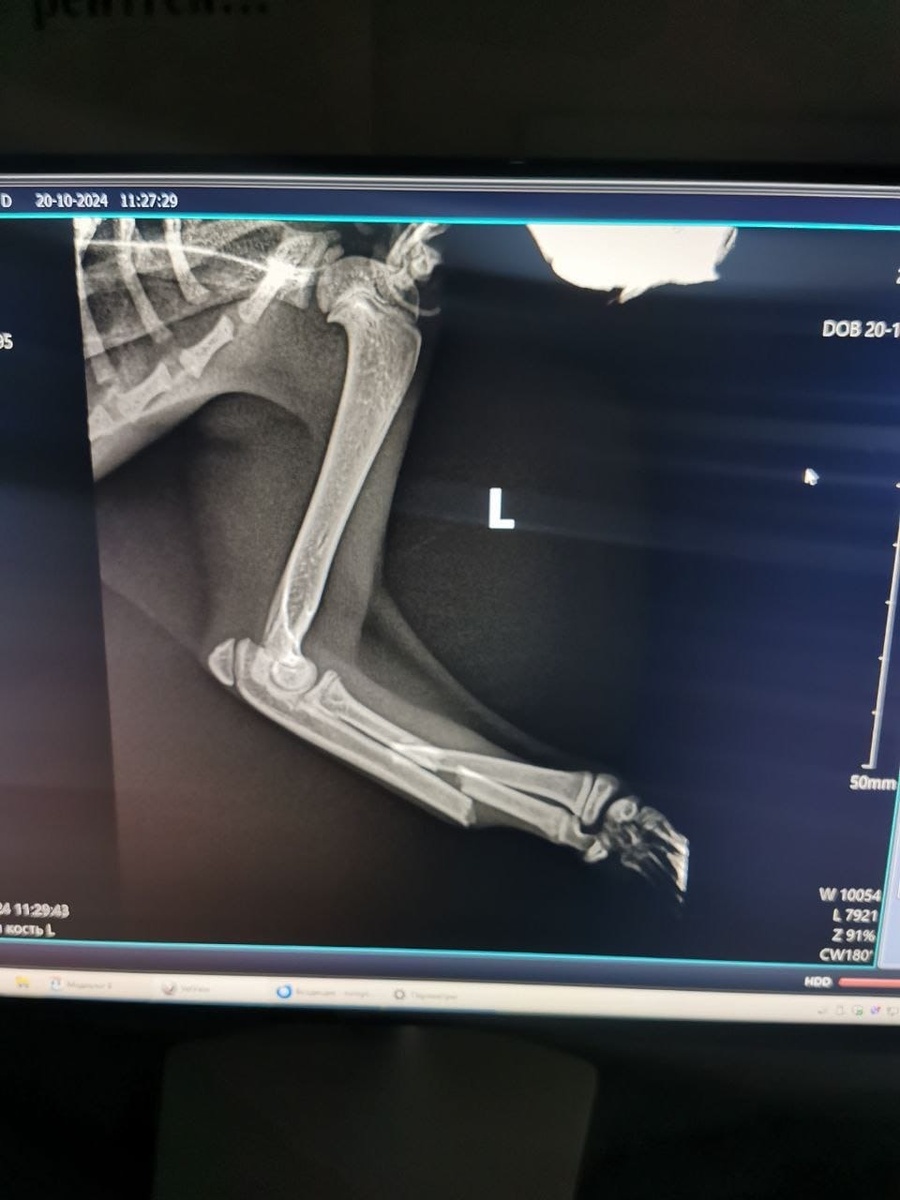

Мы забрали Бемби, отвезли в клинику, где её обследовали. Лапка котенка сильно искривлена, она не может наступить на неё СОВСЕМ... В клинике мы с Бемби прошли обследование. К несчастью, следствием сильного удара стала сложная травма - перелом предплечья, также возможно, что у малышки есть застарелый перелом. Уже завтра Бемби записана на операцию - ей просто НЕОБХОДИМ остеосинтез лапки и наложение лангеты на старый перелом, без операции крошечный детёныш ОБРЕЧЕН ОСТАТЬСЯ ИНВАЛИДОМ НА ВСЮ СВОЮ МАЛЕНЬКУЮ ЖИЗНЬ!😰

🚨‼️‼️‼️СТОИМОСТЬ ОПЕРАЦИИ СОСТАВИТ ПОРЯДКА 24 000 РУБЛЕЙ!!!